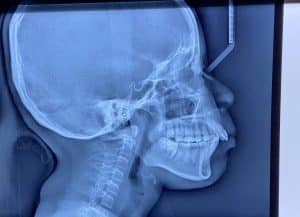

Gigi Bungsu: Dicabut atau Dibiarkan? Simak Panduan Lengkapnya

Banyak orang bertanya, “Jika gigi bungsu tidak terasa sakit, apakah tetap harus dicabut?” Jawabannya tidak selalu, namun seringkali gigi ini menjadi “bom waktu” bagi kesehatan mulut Anda.